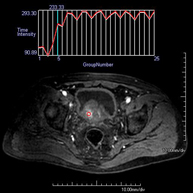

- Prostate MRI (endorectal prostate MRI + spectroscopy)

This non-invasive diagnostic procedure uses an electromagnetic field and radio waves (from a transmitter and receiver) to acquire high-definition anatomical images of the prostate gland. It is a radiation-free procedure. An endorectal coil is used to obtain images of the prostate with maximum anatomical definition, enabling a spectroscopic screening (molecular-level study to define malignant and tumour cells). A paramagnetic contrast study is also performed to provide better tissue definition. This screening takes about 40 minutes, during which time the patient should remain as still as possible. Prior preparation requires colon cleansing. This test is especially recommended for patients with suspected prostate cancer, known prostate cancer for tumour staging, prostate tumour localisation as a guide or map for biopsy, follow-up of patients with prostate cancer treated with surgery or radiotherapy, suspected recurrence of prostate cancer, etc.